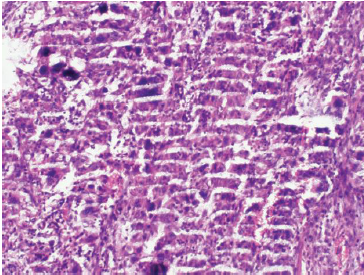

七、切片染色效果不佳

切片染色效果不佳可能是由于染色時間過長或過短、染色液濃度不合適等原因造成的。